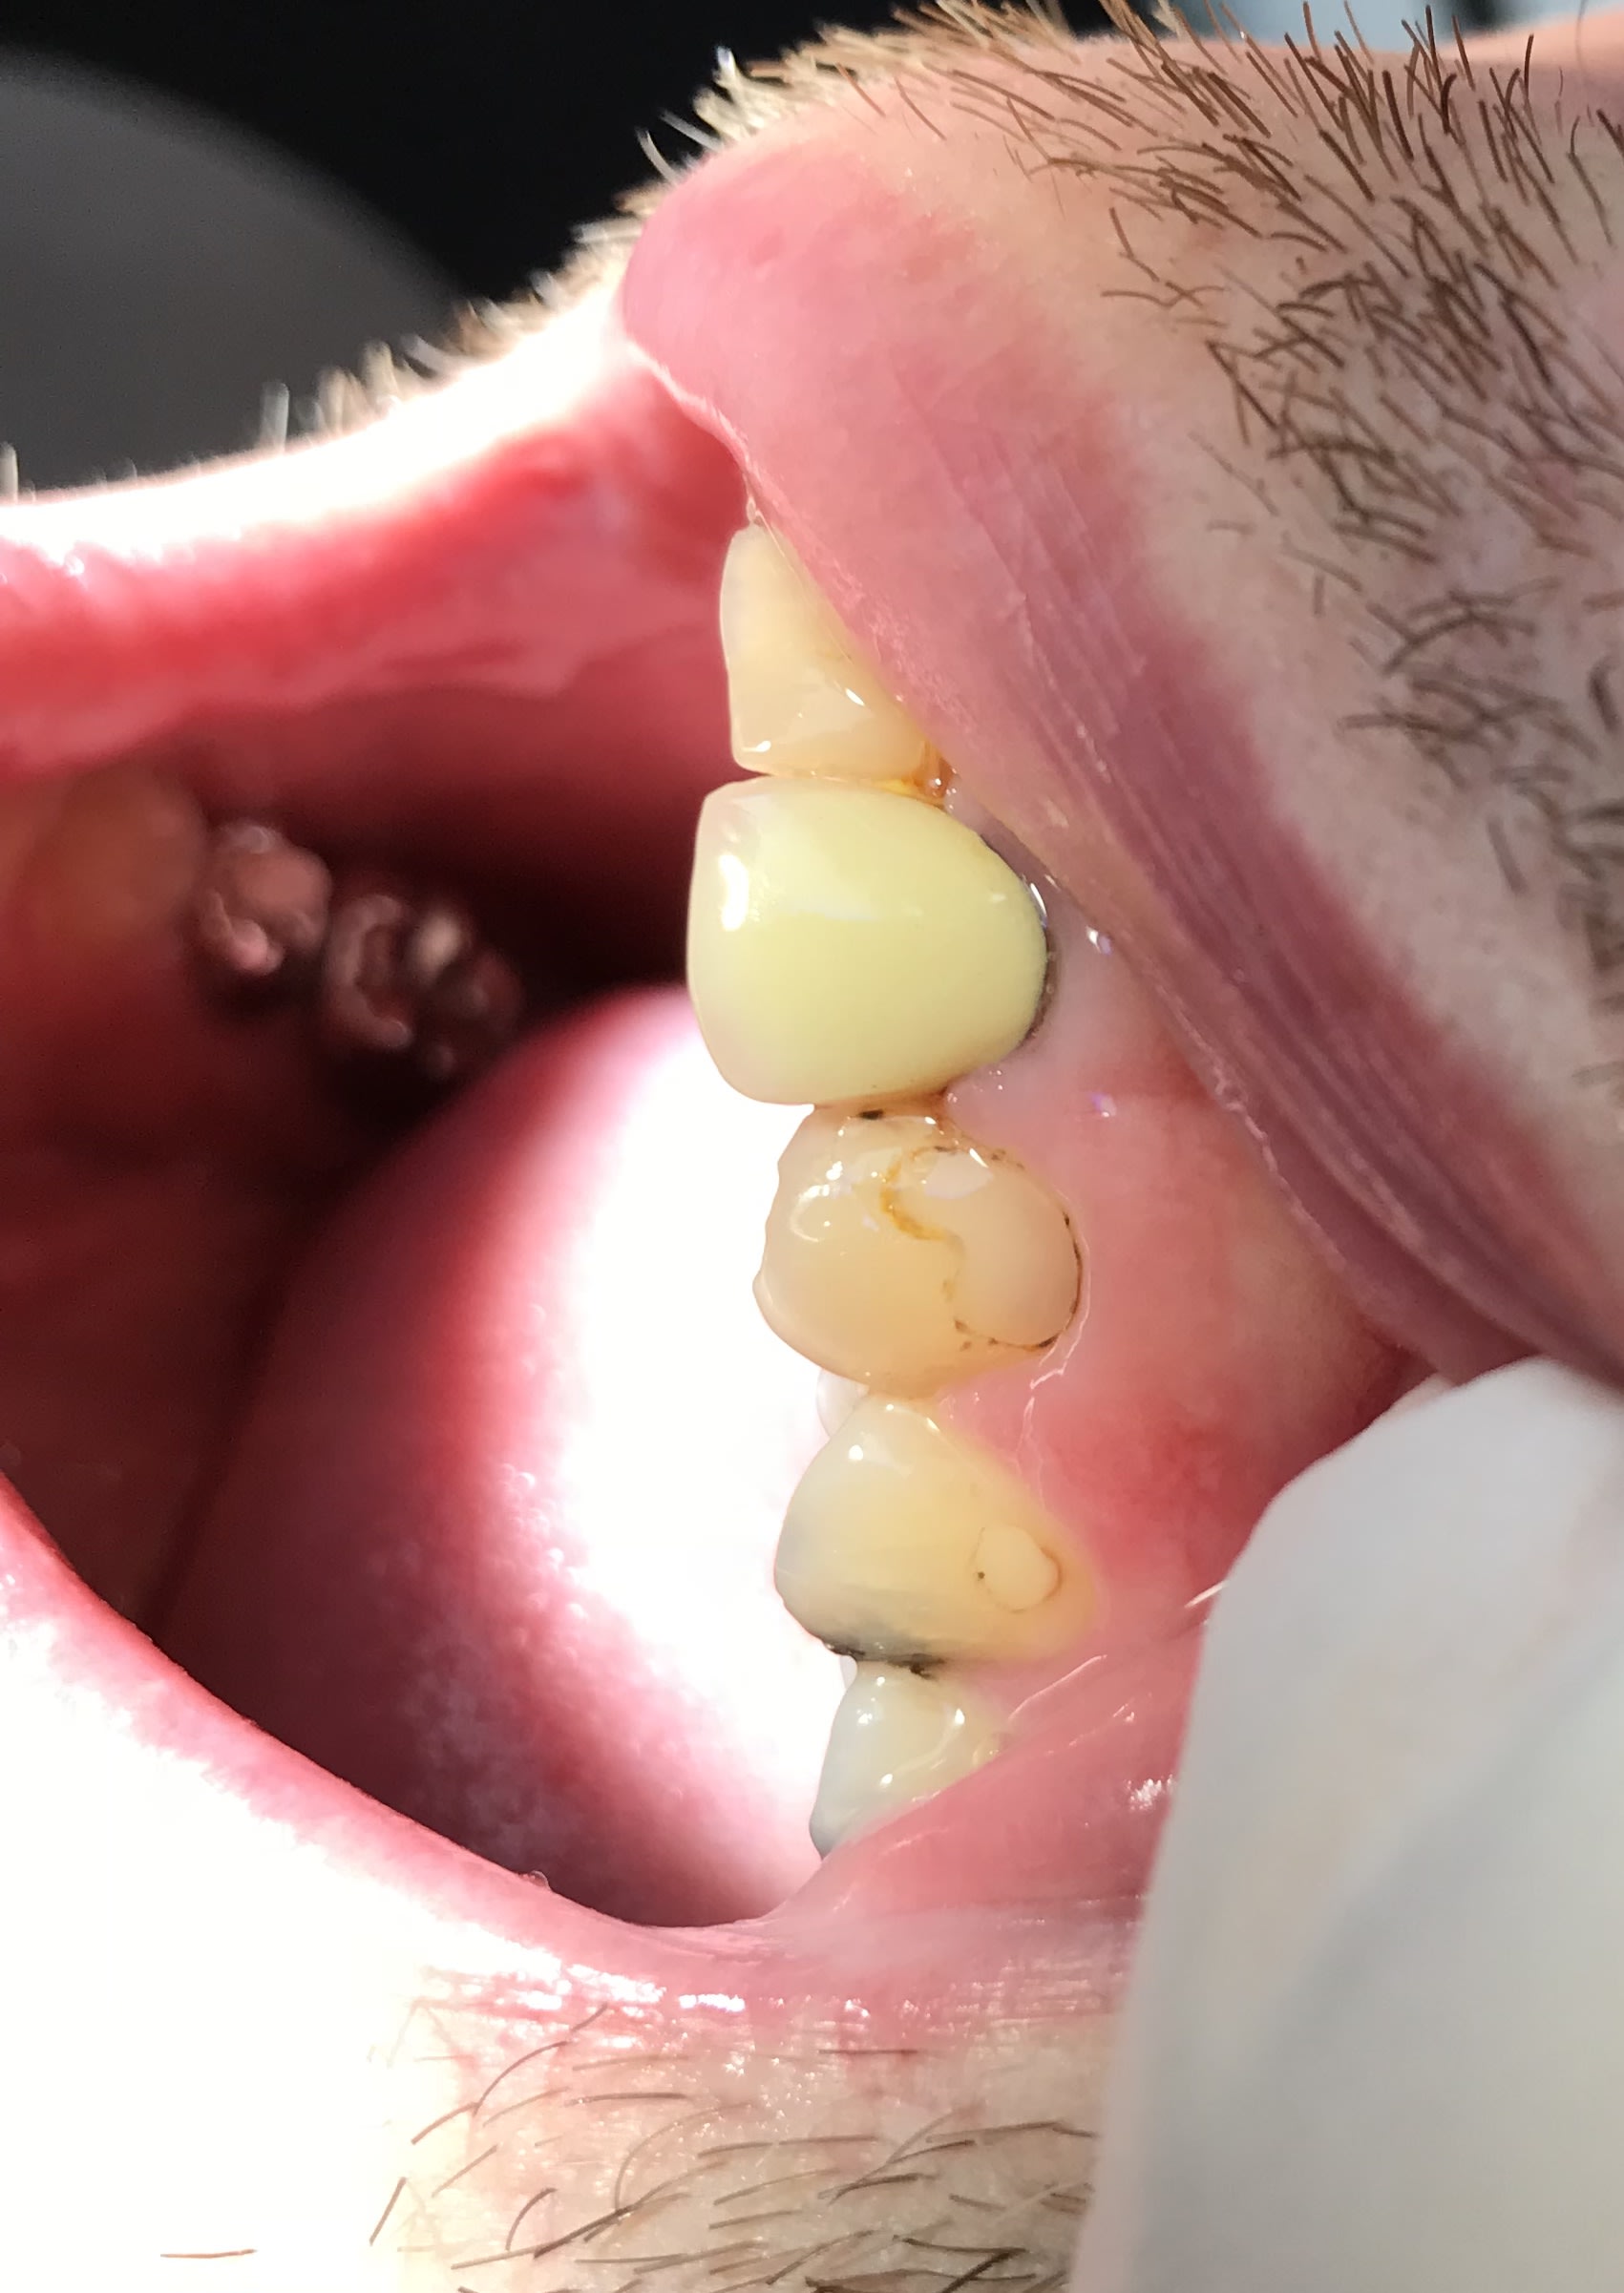

Ah c'est vrai qu'ils sont beaux les composites !!! 😊

Img 0300 oxxxsy - Eugenol

Potentiellement, tu t’en tire souvent avec un polissage dans ces cas là. Après pour 20 euros, tu 'auras pas un protocole parfait avec parfois un adhésif 3 en 1, et peu de perte de temps à finir la polymérisation en surface sans oxygène.

Je ne sais pas si c'est un MR3 qui a été utilisé dans ce cas . Mais rassurez vous avec les MR3 il y a aussi ça. 

Très très joli

Ça vieillit très bien le composite .....